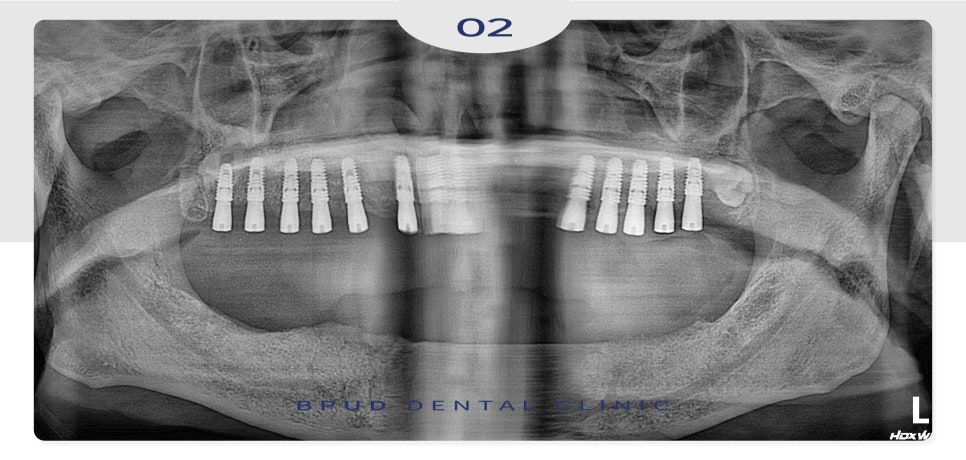

23.06.05

식립할 개수가 많다 보니

위쪽 먼저 식립하고 일주일 뒤

아래쪽을 진행하였는데요.

23.06.12

아래쪽까지 식립을 마친 후에는

잇몸뼈와 인공치근이 단단하게

융합되는 기간으로

약 4~5개월 동안 임시틀니를

제작하여 사용하실 수 있도록 하였습니다.